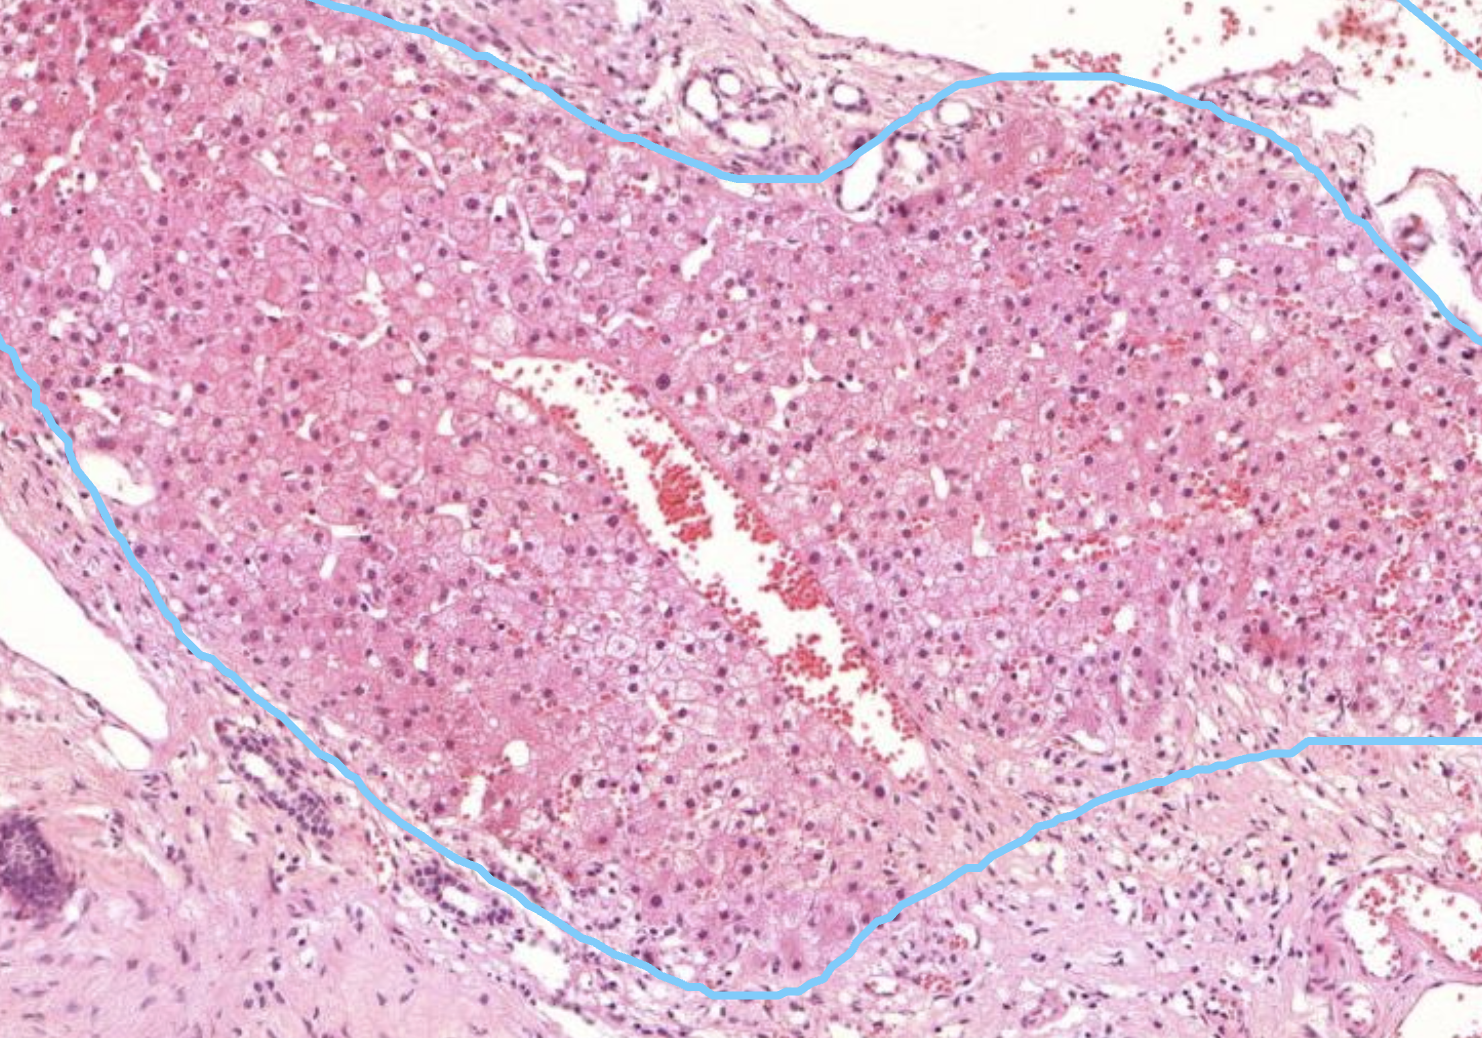

40) Um welches Gewebe handelt es sich hier?

Histopathologisches Bild: Kolonschleimhaut

Hier zu sehen ist eine Lebergewebe.

Erkennbar an den Sinusioiden und der Struktur der aneinander haftenden Zellen. Mittig erkennt man eine Zentralvene

40) WElches Präperat ist hier zu sehen?

Kavernöses Hämangiom.

Es zeigen sich unterchiedlich weite Blutgefäße und darin ganz viele Erythrozyten.

Wenn diese Gefäße super groß werden, dann nennt man die Kavernös. Vaskuläre tumoren sind in der Leber recht häufig